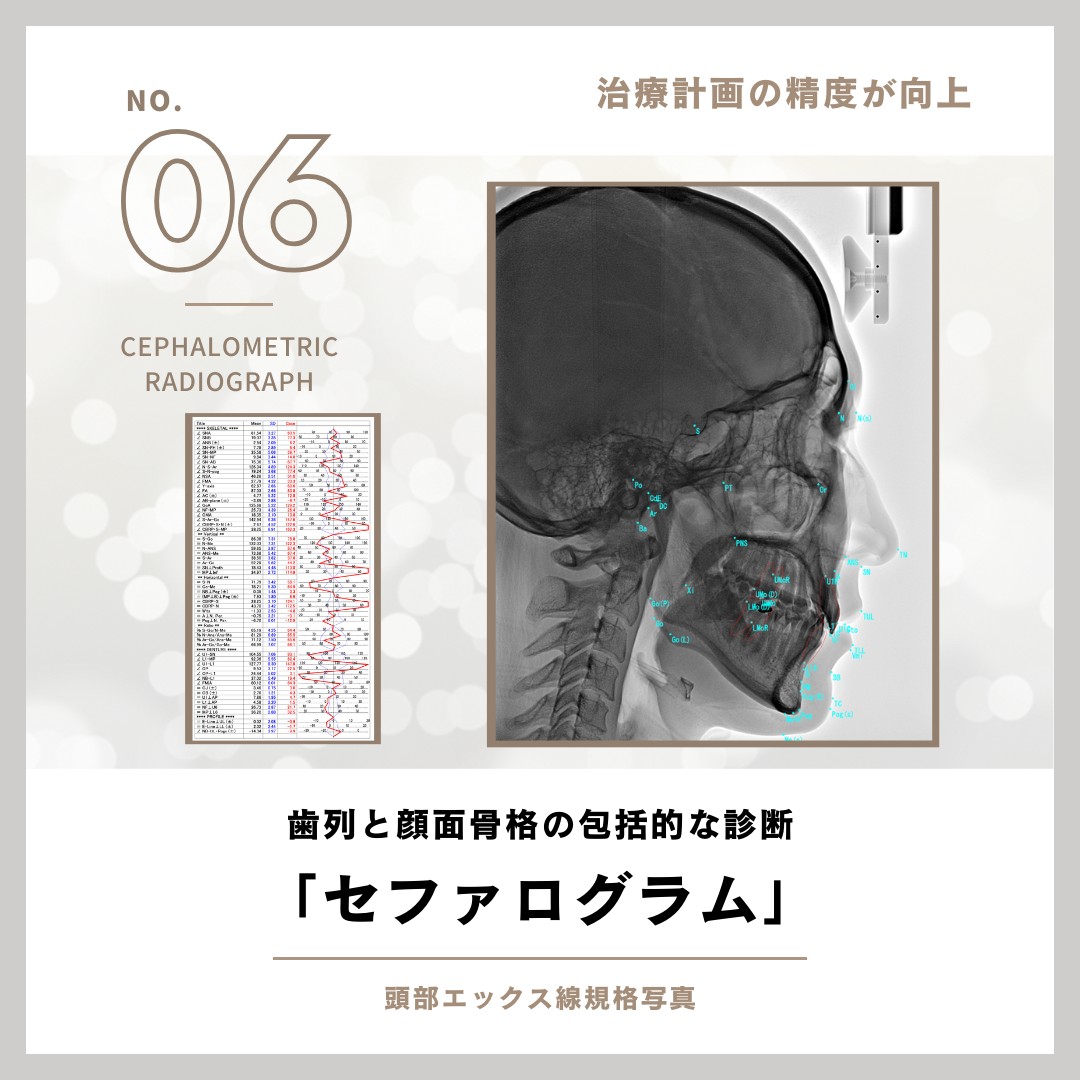

駒沢よしや矯正歯科では、精密検査の一環として頭部エックス線写真(セファログラム)を撮影しています。この検査は、顎や歯の状態を立体的かつ詳細に把握するために欠かせない重要なステップです。

6 頭部エックス線写真(セファログラム)

セファログラムとは?

セファログラムとは、頭部全体を横から撮影する特殊なエックス線写真です。これにより、以下のような情報を得ることができます。

顎の位置関係の分析

上下の顎骨のバランスや位置を確認します。

歯列と顔面の骨格の関係

歯並びが顔の骨格とどのように調和しているかを分析します。

治療計画の精度向上

患者さま一人ひとりに合わせた矯正治療計画を立てる際に役立ちます。

セファログラムの役割

正確な診断

セファログラムは、目に見えない骨格や咬み合わせの問題を正確に診断するために使用されます。

治療効果の測定

治療前後で撮影することで、矯正治療がどれだけ効果を上げているかを科学的に評価できます。

将来の成長予測

特にお子さまの場合、成長に伴う顎や歯の変化を予測し、治療タイミングを見極めます。

快適な撮影環境

駒沢よしや矯正歯科では、エックス線撮影機器を導入し、短時間での撮影が可能です。また、放射線の被ばく量を抑えた安全な撮影を心がけています。

セファログラムが必要な理由

矯正治療は、歯並びだけでなく顔全体のバランスを考慮して進めるものです。そのため、セファログラムは治療の基盤となる大切な情報を提供します。

安心・安全な検査環境で、正確な診断と効果的な治療計画を。7 歯科用CT

セファログラム(頭部エックス線規格写真)・歯科用コンビームCT

矯正治療では、歯並びだけでなく、あごの骨格や歯の位置を丁寧に確認することが大切です。必要に応じてセファログラムや歯科用コンビームCTを用い、診断と治療計画に役立てています。